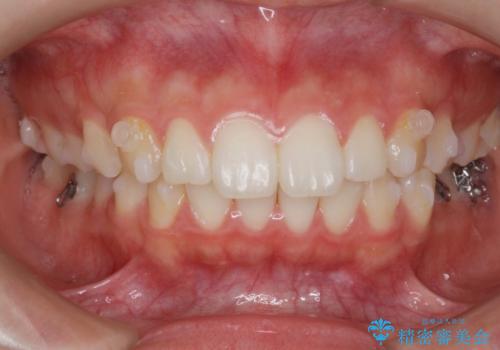

矯正治療を途中でやめてしまった、途中からの治療希望

- 他院での矯正治療中に行かなくなってしまい、装置をつけたまま矯正治療の続きを希望され来院されました。

マウスピースでは並べることが難しい左下の奥歯を部分ワイヤー矯正で並べたのち、マウスピース矯正装置インビザラインで歯並びを整えていきます。